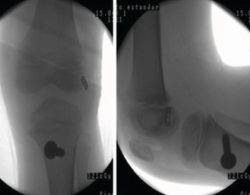

Shelbourne et al.(76) publicaron buenos resultados en 16 pacientes tratados con autoinjerto rotuliano con técnica transfisaria tibial y femoral, sin encontrar casos de deformidad ni de discrepancia de la longitud de los miembros (Figura 7).

Figura 7. Esquema de la técnica transfisaria.